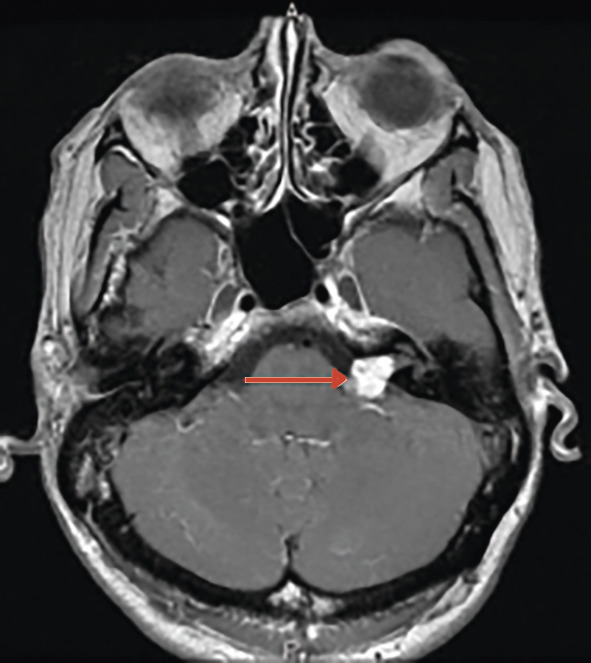

Otospongiose :

– ostéodystrophie de la capsule labyrinthique, responsable d’une ankylose de l’étrier et donc d’un défaut de transmission des sons vers l’oreille interne ;

– à prédominance féminine, aggravée par les épisodes de la vie génitale (grossesse surtout) ;

– le caractère familial – bien que non systématique – est très évocateur ;

– diagnostic confirmé par le scanner des rochers (fig. 2 ) ;

– prise en charge chirurgicale.